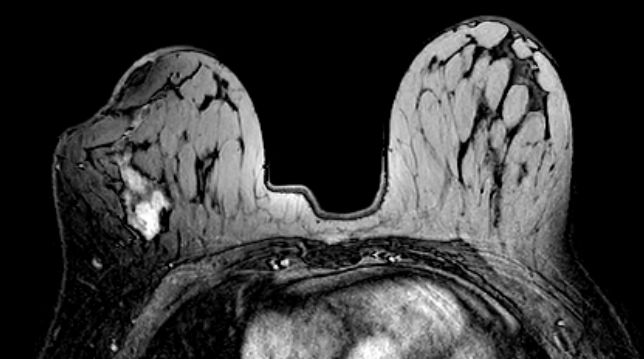

zurück MRT der Brust

Malignitätskriterien

• unregelmäßige Form

• unregelmäßige Begrenzung

• heterogene Ausdehnung

• Typ - 3 - Ausdehnungskinetik